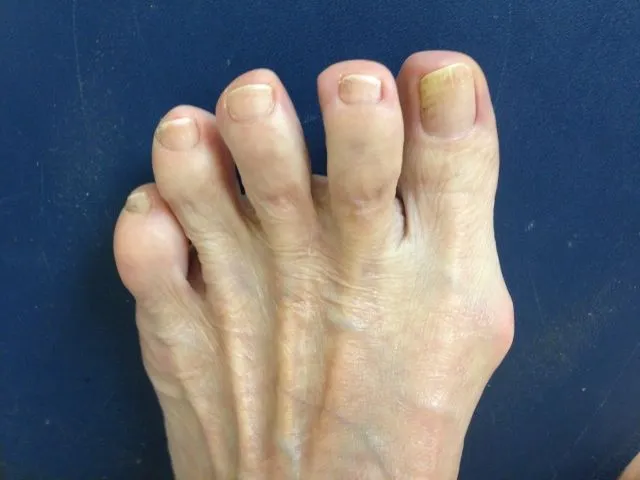

Before and 6 months status post bunionectomy.

Series of Bunionectomy with First Metatarsal Osteotomy (OW)

Pre and Postop Xrays

Preop Clinical Pics